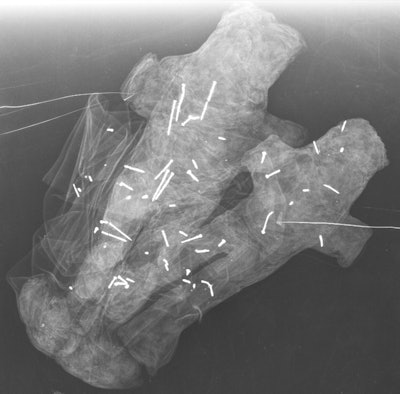

Three dolls made of red fabric.Finally, the paired dolls were not clearly identifiable as male or female, they wrote. The fact that they are a duo could signify a couple, a father and son, or siblings. The researchers found 58 needles in these two dolls: 20 in the white doll, 33 in the black doll, and five scattered across the fabric of each.

Doll pair made of black and white fabric.

Doll pair made of black and white fabric.Cracking the code